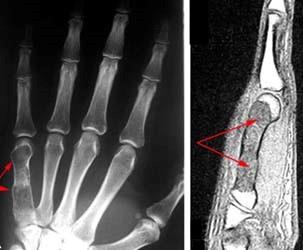

Enchondromas can occur in anyone but are most common in middle-aged patients. They are most often found in the small bones of the hand. In fact, enchondroma is the most common bone tumor of the hand. Enchondomas can also develop in the body's long bones, such as the femur (thighbone), tibia (shinbone), and humerus (upper arm bone).

X-rays. X-rays provide images of dense structures such as bone. On X-rays, enchondromas appear as small (less than 5 cm), lobe-shaped, darkened tumors in the middle of the bone. They usually contain white spots or calcification within. The white areas of the tumor show a pattern of rings and arcs that indicates the tumor contains cartilage.

Other imaging tests. Your doctor may order a computerized tomography (CT) or magnetic resonance imaging (MRI) scan to help further evaluate your tumor. These scans give a more complete picture of the bone around the tumor. If the tumor has turned into a malignancy, the scans may show bone erosion, bone inflammation, or a mass growing outside the bone.